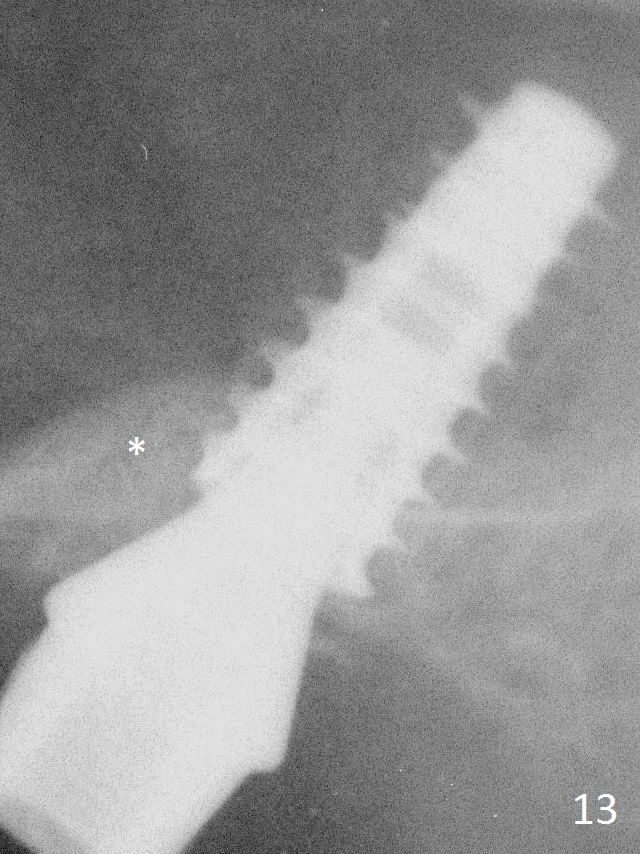

The bone density in the mesial socket appears to increase and becomes more homogenous 3 months postop (Fig.13 *). Impression is taken for final restoration.